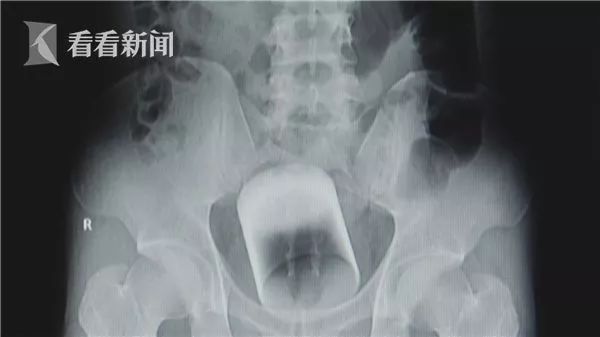

看看新闻报道,小张从肛门塞入玻璃杯并使其在体内滞留两天,疼痛难忍之下来到医院就诊,但是因为杯体太滑无法取出,医生只好采取开腹手术才顺利取出。

相关医学人士表示,肛门塞异物是非常危险的行为,轻则可能造成直肠粘膜受伤出血、肛裂出血、肛门失禁,严重则会刺穿直肠引发腹膜炎,危及生命安全。